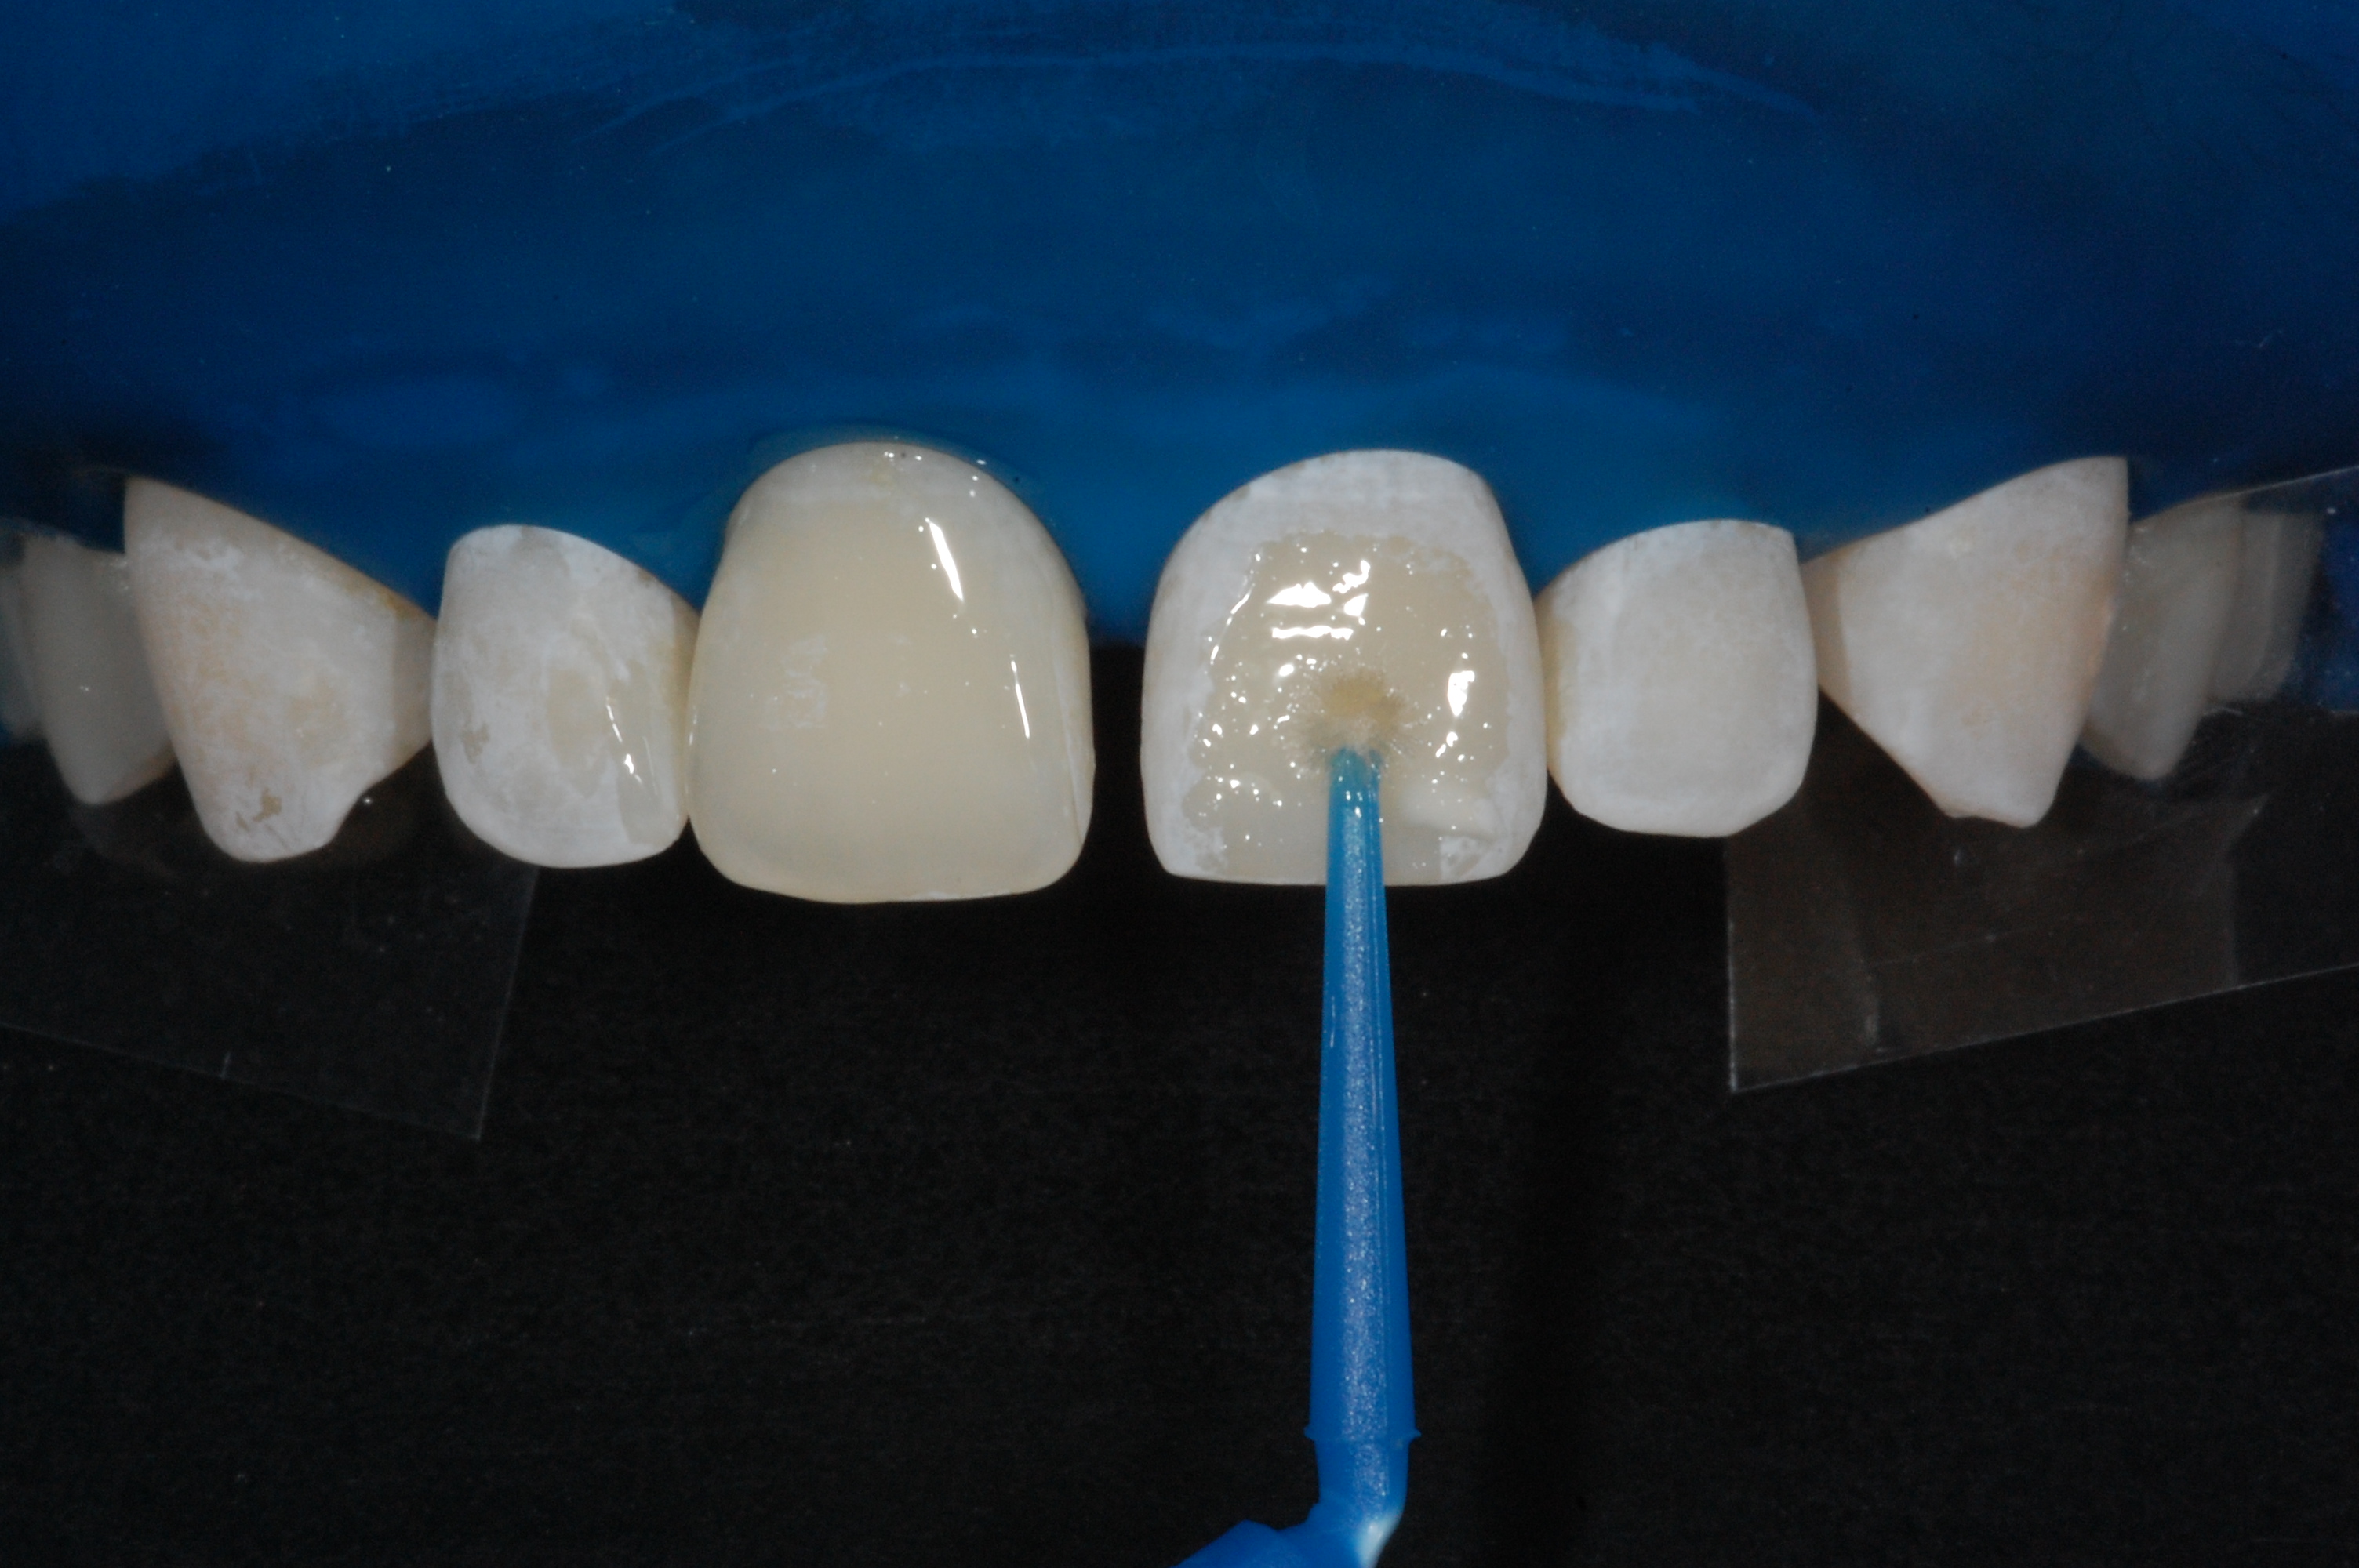

The presence of diastema, between anterior teeth, distorts a pleasing smile by concentrating the observer’s attention on the spaces. The patient’s needs and expectations must be considered in the process of treatment planning to ensure satisfaction with the treatment outcomes. There are many forms of therapy that can be used for diastema closure. A carefully developed diagnosis, which includes a determination of the causal elements and advanced treatment planning, allows the most appropriate treatment to be selected for each case. The aim of this paper is present a multidisciplinary approach as a solution to multiple diastemas in the anterior region using gingival tissue recontouring and direct adhesive restorations, with minimum wear of the dental structure, after the orthodontic intervention discussing the minimal intervention to obtain imperceptive and aesthetic final restoration. Thirty-six months after the treatment was carried out, the final aesthetic was maintained with all dental element details and gingival tissue harmony, without recurrence of periodontal pockets and the preservation of the tooth color and shape.